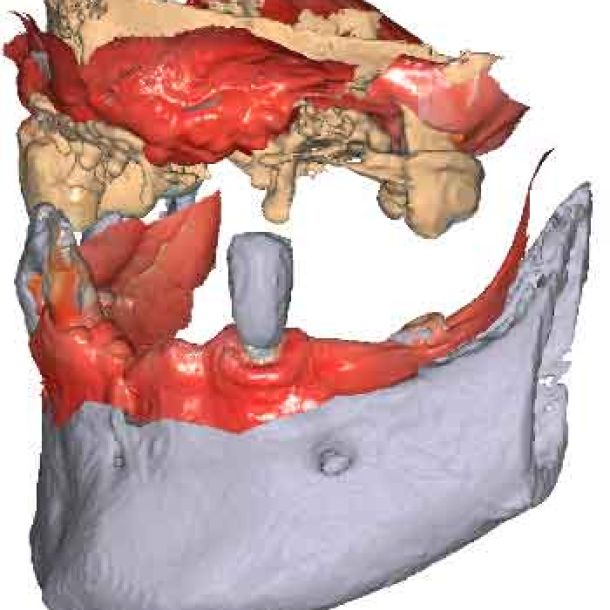

When traditional IOS scans lack necessary references, Cone Beam Computed Tomography (CBCT) data serves as a possible alternative. By utilizing CBCT scans, clinicians can establish accurate reference positions for treatment planning.

To be able to use CBCT data as initial models, we need to transform the DICOM file into an STL file.

By importing patient DICOM files instead of the IOS scans, clinicians can register jaw motion, facilitating precise treatment planning.

Import the segmented and converted CBCT models as initial models in TWIM